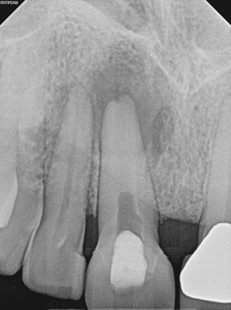

Treatment Rendered: Sometimes we have the opportunity to combine multiple treatment strategies in complex cases. In this case, non-surgical retreatment of #8 was performed in tandem with decompression. After discussing his treatment plan with the referring GD, the patient was seen first by his GD for removal of the existing crown and placement of a long-term milled temporary crown. The patient then returned to our office for the post and gutta-percha removal with placement of intracanal calcium hydroxide. This was followed by immediate decompression of the lesion. The decompression technique used was the simultaneous needle aspiration and irrigation method described by Hoen et al. (JOE, 1990). This involves placement of two 16 gauge needles into the lesion with simultaneous aspiration and irrigation with saline (no long-term drain was used). 30ml of saline was used to irrigate the lesion until the aspirated fluid was clear.

After one month, the patient returned for follow-up and the buccal sinus was still present. The tooth was re-accessed and the calcium hydroxide was replaced. At the two month mark, the buccal sinus tract was healed, but the canal still had continued mild drainage internally. A third round of calcium hydroxide was applied and left in place for 3 months. When the patient returned (5 months after initiating treatment), evidence of healing was observed radiographically around #7 and #8. RCT #8 was completed with an MTA obturation and RMGI orifice barrier. Sufficient ferrule and peripheral tooth structure was present and another post was considered not necessary.

After 2 months of calcium hydroxide. Early evidence of periapical healing, The buccal sinus tract healed but the canal was still draining internally. PA taken immediately after third round of calcium hydroxide (powder) applied.